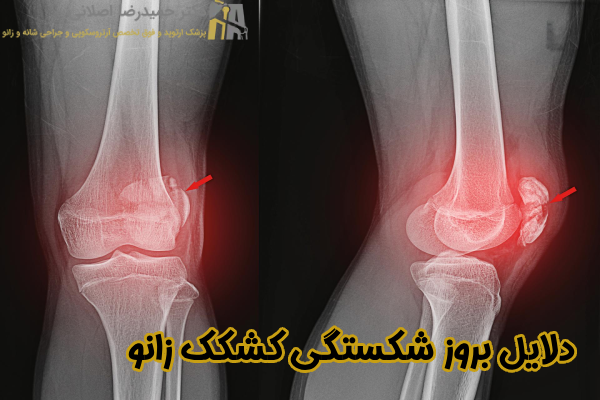

دلایل بروز شکستگی کشکک زانو

بهتر است بدانید شکستگی کشکک زانو در نتیجه آسیب های فیزیکی شدید به این ناحیه رخ می دهد که در ادامه به برخی از مهمترین علل بروز این عارضه اشاره می نماییم:

- کاهش تراکم استخوان

- ضربات مستقیم و شدید به زانو

- زمین خوردن یا افتادن بر روی زانو

- انقباض ناگهانی عضلات چهارسر ران

- عوامل مرتبط با سبک زندگی و داروها